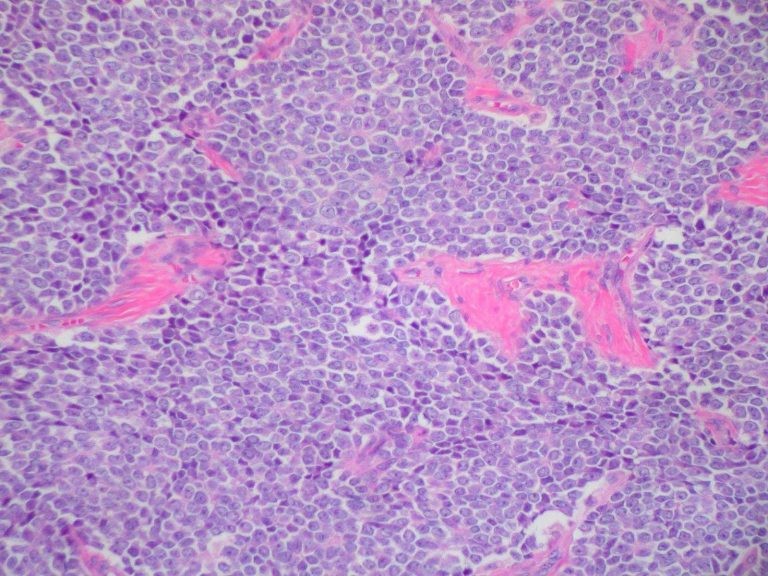

Cos’è il sarcoma di Ewing

Come riportato da airc.it, il sarcoma o tumore di Ewing si riferisce ad un gruppo di tumori con origini e caratteristiche genetiche e cellulari simili, descritti per la prima volta dal patologo americano James Ewing all’inizio del secolo trascorso. I tumori di Ewing possono svilupparsi attorno alle ossa o ai tessuti molli e possono essere localizzati in qualsiasi parte del corpo, ma più comunemente si verificano nella tibia, nel femore, nel bacino e nelle costole. Questa grave patologia può manifestarsi a tutte le età, ma si presenta soprattutto nei bambini e negli adolescenti.